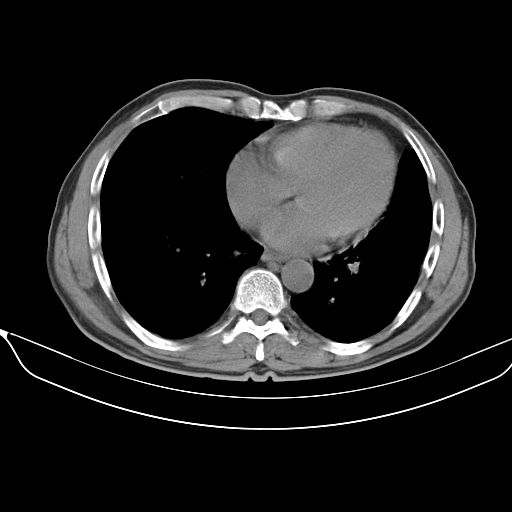

以下是引用心路寻觅在2010-3-1 10:23:00的发言:[br]1、考虑左肺上叶周围型肺癌[br]2、右上肺陈旧性病灶。[br][br][本贴已被 心路寻觅 于 2010-3-1 10:40:18 修改过]

以下是引用shuiyuan在2010-3-1 10:45:00的发言:[br]考虑左肺上叶中心型肺癌伴阻塞型炎症,邻近胸膜受侵。